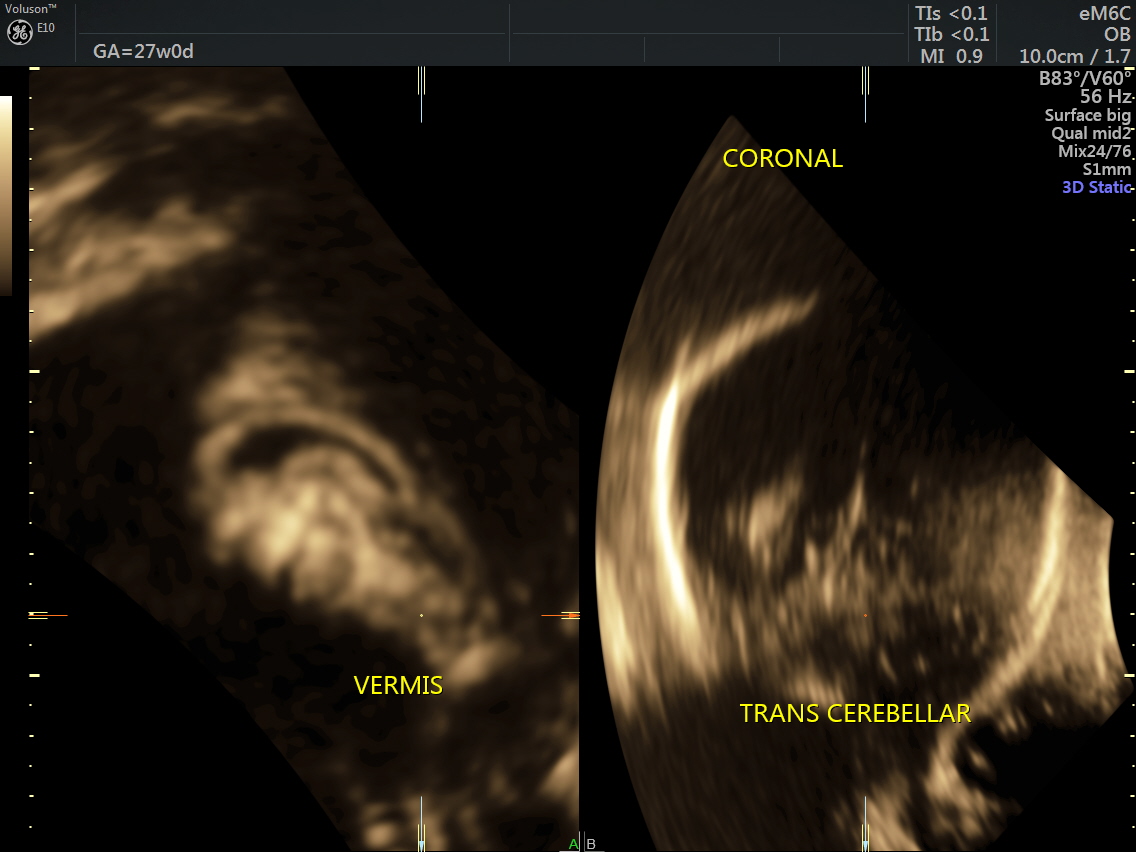

RT AORTIC ARCH_30 Published June 17, 2016 at 1136 × 852 in Rt aortic arch and aberrant left subclavian artery ← Previous Next →